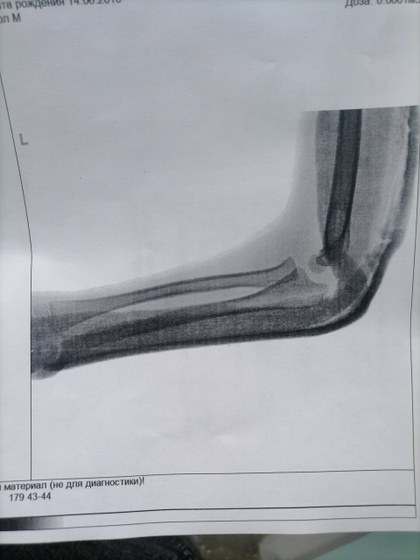

Сходили мы с переломом локтя 12 на прием, все было ок, гипс слегла помятый, сказали сходите на ренген и псм надо ли заменить его, сходили. Сказали все хорошо 29 приходите на снятие, ну мы спокойной и поехали домой, наступает 13,14 число и вот сегодня встаём все с утра и понимаем что гипс сломан в локте прям сгибе прямо, поехали мы с сыном в травму снова, пришли отправили к дежурному травмотологу осмотрел, спросил был ли 12 такой же он гипс? , я тип нет так не ходил, но был изломан внешне деформмрован, сказали не надо менять,отправили по итогу нас сразу поменять гипс, уехали мы домой. Сын встал рано, уснул в 3 часа где то дня, проспал 1.5ч - встал, пошли мы на улицу и он снова нам такой говорит смотрите снова качается гипс тип, мы такие в аху* как так то делают, даже сутки гипс не поддержался… Завтра поедет муж и скажет чтоб забинтовали не вот лангету на заднюю поверхность, а обмотали руку прям, 2 недели ходить ещё, не будем же ежедневно менять ездить его эту лангету.